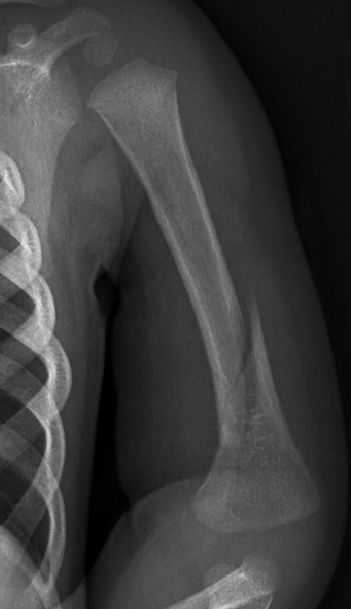

Fraktur humerusdiafys

1-årigt barn med diafysär humerusfraktur, fick vadd runt armen och linda runt kroppen i 3 veckor, därefter kliniskt läkt.